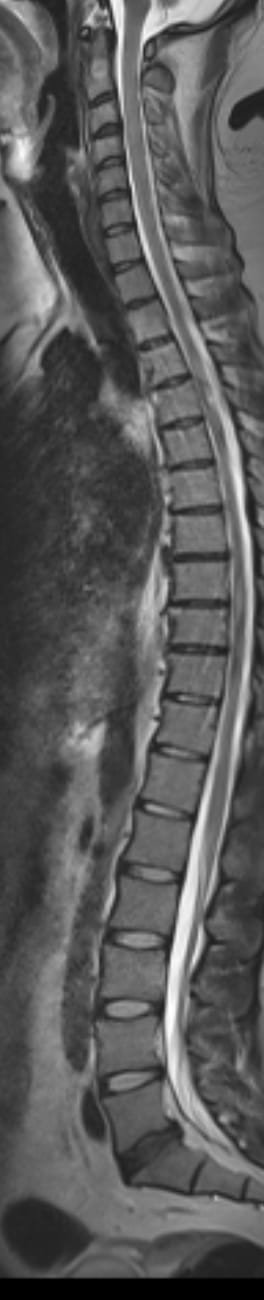

The overall alignment looks fairly straight. No obvious severe scoliosis or major vertebral slippage (spondylolisthesis) jumps out on this single view.

The spinal cord looks continuous and centrally located. The bright CSF column around it appears preserved along most levels, which usually suggests no severe central canal stenosis at a glance.

Several discs appear a bit flattened with reduced height, especially toward the lower thoracic / upper lumbar region. That’s commonly seen with degenerative disc changes, particularly with age.

There are mild posterior disc bulges at a few levels (they subtly indent toward the canal), but I don’t see an obvious large herniation crushing the cord on this image alone.

Heights look generally maintained. No clear compression fracture is obvious on this slice.

there is no water in several of those discs. this is absolutely a case of degenerative disc disease